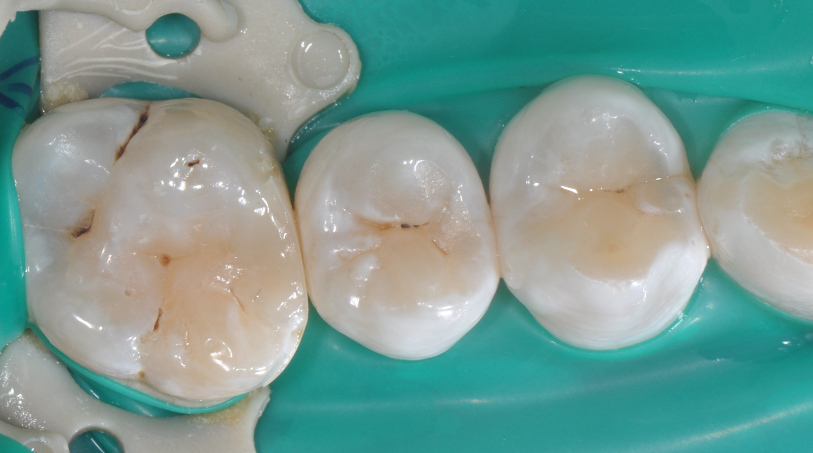

◆该成形片能更好的将龈缘区域的边缘封闭性做的更好。尤其是在邻面区域,涂布第六代粘结剂,固化粘结剂之后,配合高填料流体树脂和后牙专用树脂进行该洞形的充填。

◆术后即刻照,如果邻面边缘出现悬突,可以使用12#手术刀去除,再配合抛光条抛光

◆术后撤离橡皮障后口内照片,术后1周复查,我们修正了边缘嵴的斜度及邻面轴线上的多余材料;复查是很重要的,能够发现第一次操作的时候遗留的不足,并且再次修正,保障了充填体的寿命。该案例也得益于改善了的成形片,修正了以往的成形片邻面龈缘区域材料残留形成过多的悬突材料,避免了术后龈乳头炎的发生!